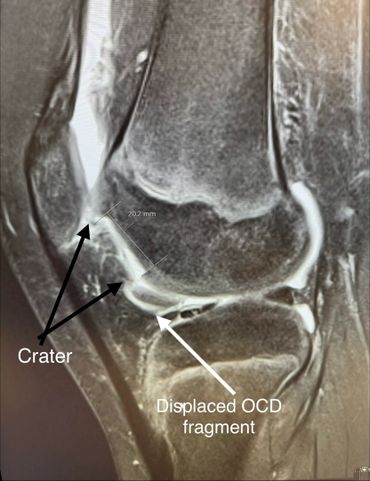

- Osteochondral OCD repair